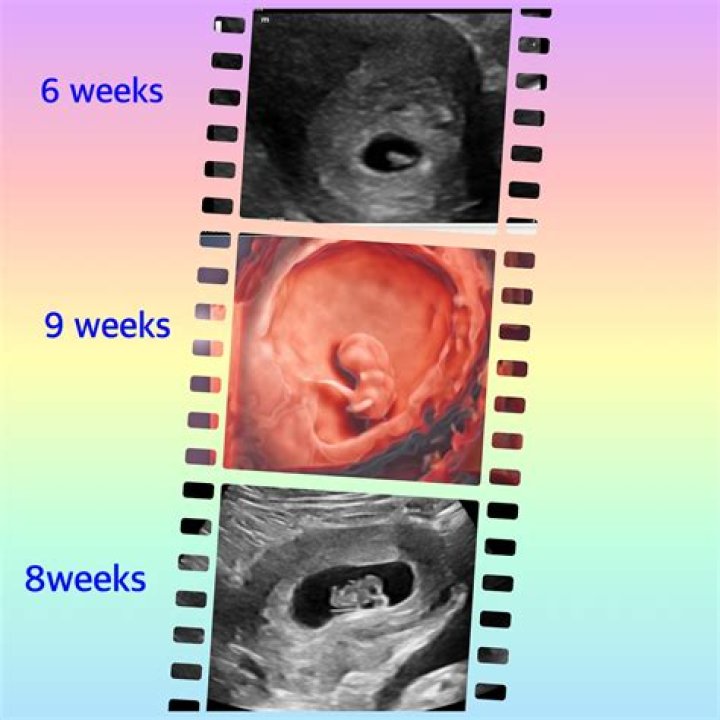

How accurate is the ultrasound examination? Ultrasounds performed during the first 12 weeks of pregnancy are generally within 5 days of accuracy. The most accurate time is between 8 and 11 weeks gestation. This is because the baby is growing so quickly that there is a big difference in size from week to week.

Can you see anything on a 9 week ultrasound?

At nine weeks, you will be able to see your baby’s head, body and limbs. You will also be able to hear your little one’s heart beat for the first time with a Doppler monitor.

The embryo’s heart begins to beat around 6 weeks of pregnancy – sometimes earlier, sometimes later. A transvaginal ultrasound (an internal ultrasound) can detect a heartbeat around 6 weeks of pregnancy. However, it isn’t uncommon to be unable to detect a heartbeat via ultrasound until closer to 7 or 8 weeks.